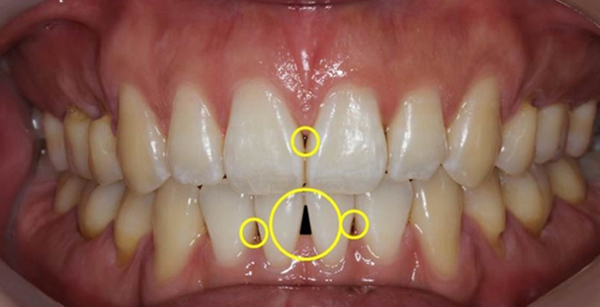

앞니는 정면에서 보았을 때 정사각형이 아닌 잇몸 쪽이 뾰족한 오각형 모양에 가깝다. 따라서 가까이 붙어있는 두 치아의 하방에는 공간이 생길 수밖에 없는데, 보통 이 공간은 ‘치간 유두’라 하여 잇몸으로 메워져 있지만 사이에 잇몸 연조직이 없는 경우에는 비어있는 부위가 드러나게 된다. 이러한 부위는 하얀 치아, 선홍빛 잇몸과 대비돼 검은색 삼각형 모양이므로 ‘블랙트라이앵글(Black triangle)’이라 불린다.

치아 사이가 음식물이 낀 것처럼 까맣게 보일 정도로 벌어졌다면 치주염 등을 의심해봐야 한다/사진=사과나무치과병원

교정 중에도 쉽게 나타나는 ‘블랙트라이앵글’은 치아가 겹쳐져 있다가 교정 후 가지런히 펴지면서 공간이 발생하는 경우가 많다. 이곳은 치아가 맹출하는 과정과 더불어 잇몸으로 채워져 있어야 하는 공간이지만 치아가 겹쳐 있어서 처음부터 틈이 없어 그에 맞게 잇몸이 차오르지 않았던 것이다.

따라서 ‘블랙트라이앵글’은 교정치료의 부작용으로 잇몸이 없어진 것이 아니라 치열이 재구성되면서 잇몸의 빈 공간이 보이게 된 현상이다. 이는 특히 성인에게 잘 나타나는 편인데, 성장기 아동의 경우 비어있던 공간이라 하더라도 잇몸이 차오르며 블랙 트라이앵글이 없어지지만 성인은 그렇지 못한 경우가 많기 때문이다. 일산사과나무치과병원 교정과 김동현 원장은 “교정치료 전 진단 과정에서 잇몸의 건강 상태가 나쁜 경우 블랙트라이앵글이 잇몸병으로 인해 더 크게 나타나는 경우가 있기 때문에 교정 전 잇몸 상태에 따라 잇몸을 건강하게 치료해주는 것이 좋다”며 “치아가 틀어진 정도에 따라 블랙트라이앵글 발생은 어느 정도 예측이 가능하고, 크게 형성된 경우 치아 사이를 다듬어 다시 그 틈을 좁혀 공간을 줄여주거나 잇몸 성형으로 개선하는 것이 가능하다”라고 말했다.